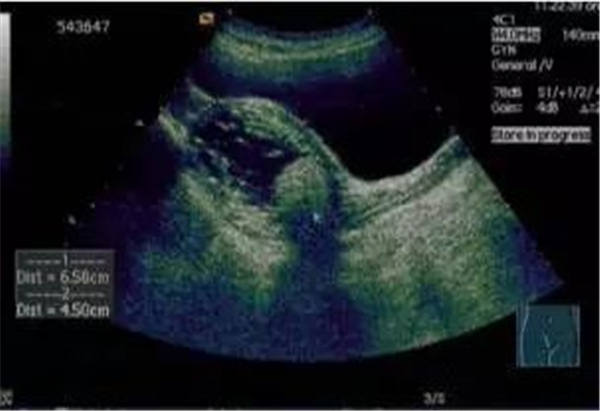

聲像圖特點:1、子宮增大邊界不規則。2、肌瘤結節呈低回聲、等回聲或強回聲。等回聲周邊可有低回聲暈呈假包膜。3、子宮內膜移位或變形。4、膀胱變形,易引起尿貯留。5、肌瘤結節周圍呈環狀及半環狀血流。阻力指數0.6±0.1。

聲像圖特征:1、子宮均勻性增大,邊界規則。2、子宮內膜線前移。3、子宮內回聲不均勻,低回聲、強回聲區,無包膜。4、子宮大小、內部回聲月經前后常有變化。5、腫塊周圍無環狀或半環狀血流,阻力指數約0.6。